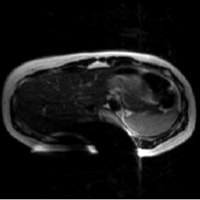

患者様を案内又は搬送する際は、患者様の金属の有無について十分注意をお願いします。金属が体内に入っている方や、 身につけている方は写真上に影響が出ると同時に体内金属が動いたり、発熱したりする場合があり危険な場合があります。 金属があった場合の症例を提示します。

ヘアピンによる影響